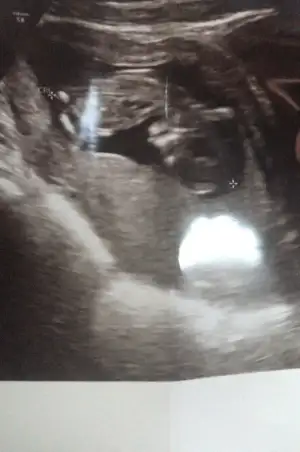

Kesın mı sizce 2 kızım var bunu da erkek istiyordum ama hayırlısı olsun saglıklı olsun inşallah

usg kafa şekli erkek nubu kız gibi canım.

Kesin diye birsey yok drlar kesin der ben tahminciyim tutabilir tutmayabilir rabbım gönlünüzdekini saglıkla nasip etsin inşallah. 11 yada 12 hafta başka usg varmı

Bende tahmin istiyorum doktor tahmin etti ama 🥰 Ikra meyra Ikra meyra